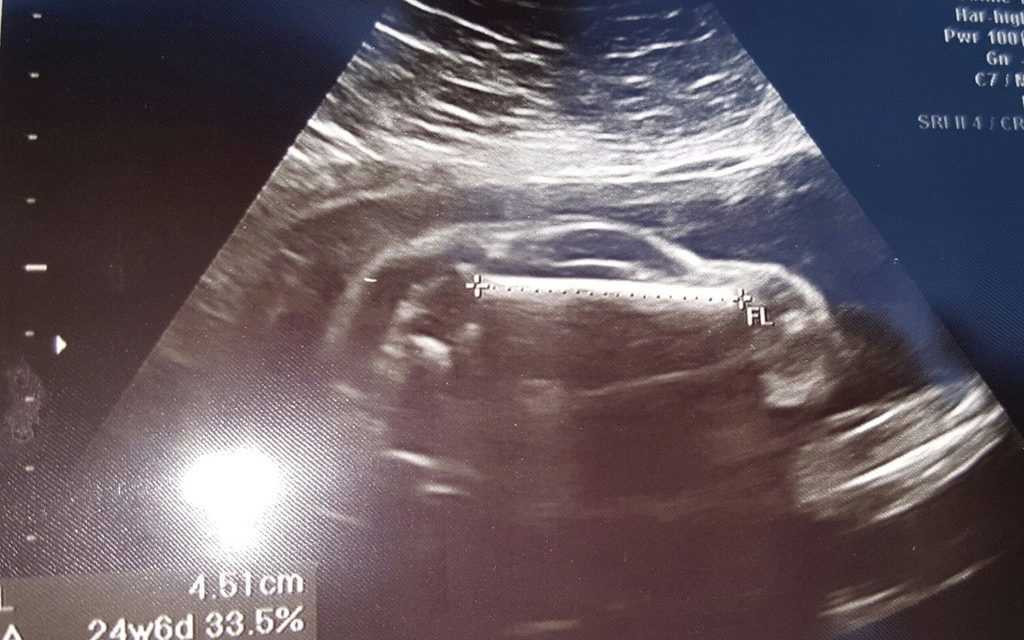

Hình ảnh siêu âm của thai phụ người Anh.

Theo đó, thay vì được thấy mắt, mũi, chân tay của con mình, đôi vợ chồng này chỉ nhận ra các bộ phận của một chiếc xe thể thao như hai bánh xe, mui xe, cửa sổ và thậm chí là một thứ gì đó rất giống vô lăng.

Nhưng khi bé mới chỉ được 6 tháng tuổi, niềm vui lại bất ngờ ập đến khi cả hai hay tin người vợ đang mang thai đứa con thứ hai. Chỉ có điều hình dạng của cái thai lại vượt quá sức tưởng tượng của bố mẹ.